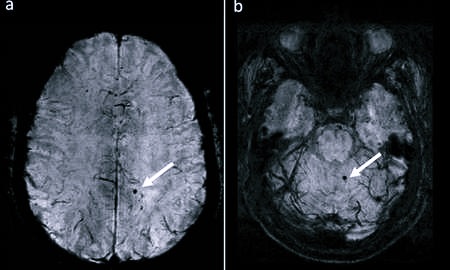

- Магниторезонансная ангиография является наиболее точным методом выполнения диагностики капилляров. Процедуру проводят посредством введения контрастной субстанции, так и без нее.